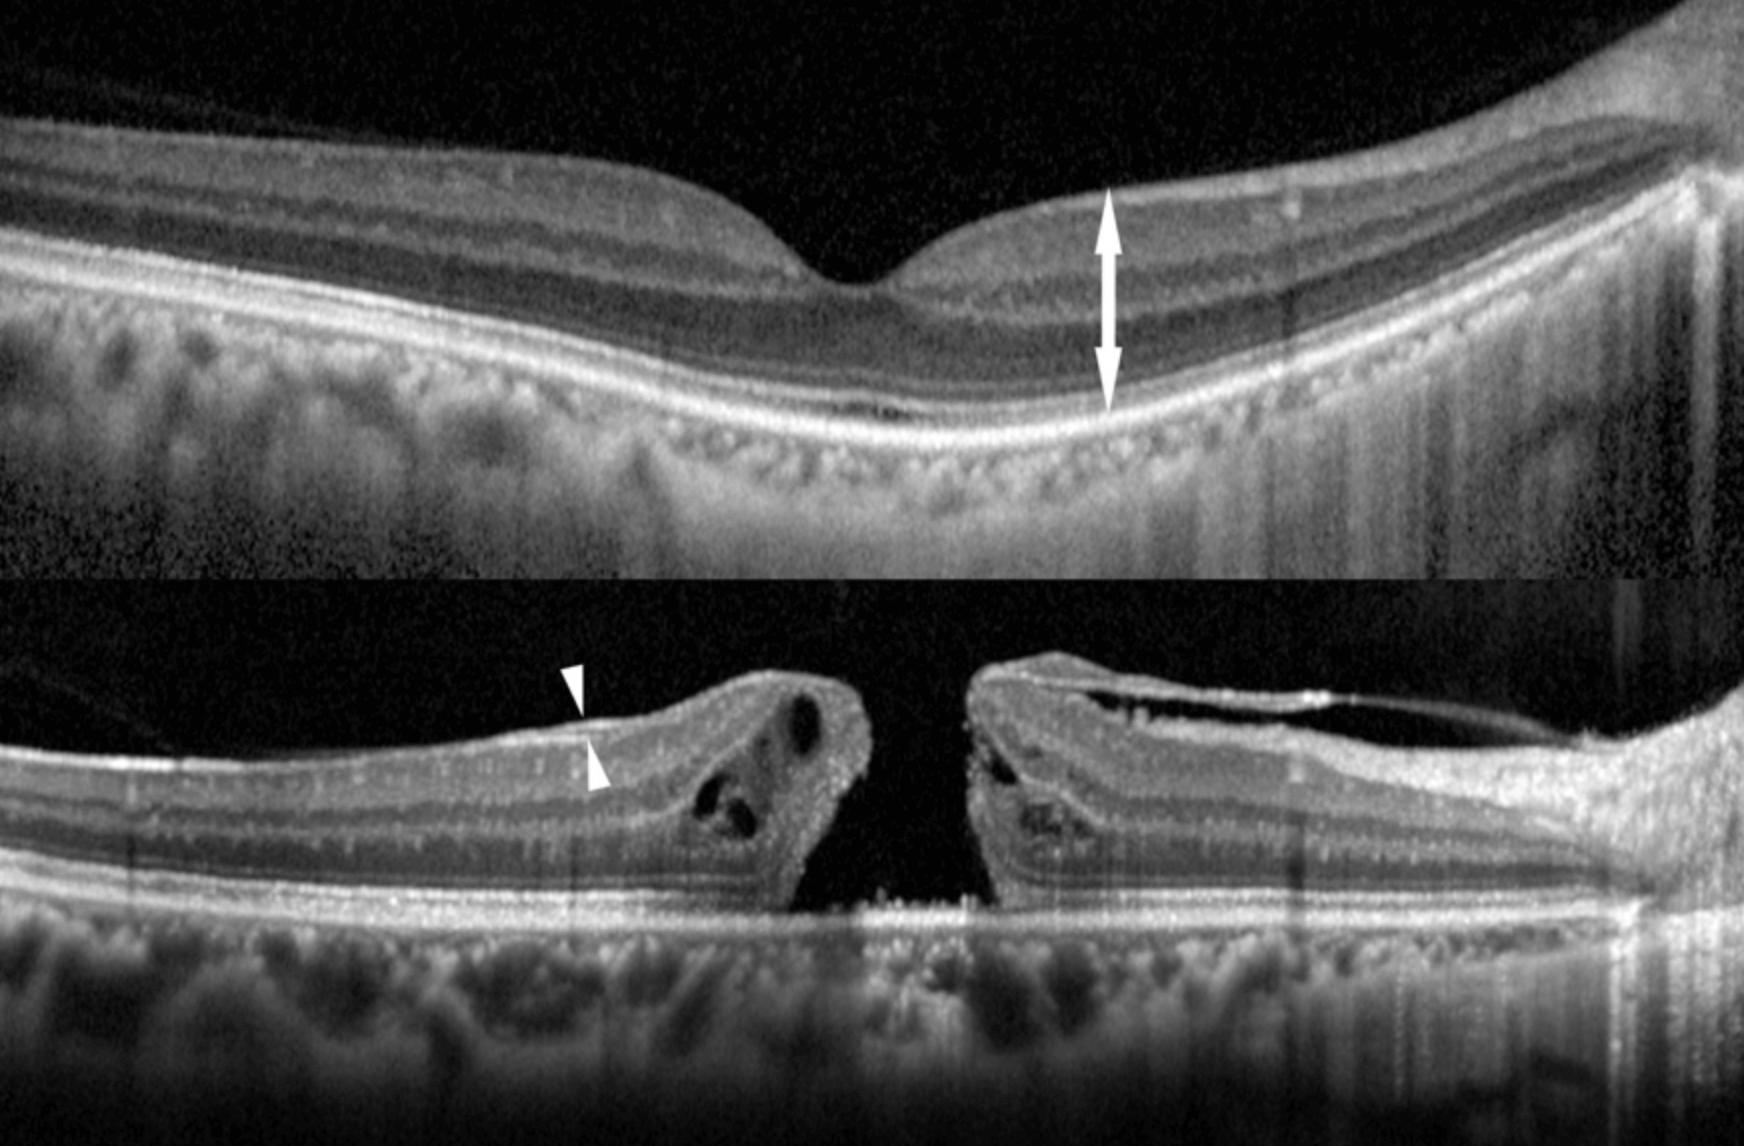

망막은 얇은 조직층으로 초점을 맞춘 이미지에 민감하고 다양한 정보를 뇌로 보내게 됩니다, 이러한 망막의 중심에는 황반이 있으며 이것은 우리가 복잡한 모양을 읽고 인식하는데 사용하는 망막의 영역입니다.

간단하게 말씀드리면 망막의 일부에 해당하는 황반부에 변화가 생기는 질병으로써, 막이 수축함에 따라 망막 조직의왜곡이 발생할수 있습니다. 이런 일이 발생하면 황반이 정상적으로 작동하지 않으며, 특히 읽기를 하거나 시각적인 작업을 하는 사람들에게 영향력을 미칩니다.

노화와 함께 눈속에 있는 젤리 모양의 유리체가 망막에서 떨어져 나가지만, 망막의 표면에 남은 유리체에 세포가 증식하여 얇은 막이 형성됨으로써 일어나며, 눈 부상이나 망막박리 수술, 다른 망막질환으로 발생할수 있습니다.

즉 후방 유리체 박리가 일어났을때에, 깨끗이 벗겨지지 않고 황반에 약간 남은 유리체를 핵으로서, 얇은 막이 생기는 이것을 망막 전막이라고 합니다.

망막전막의 초기에는 자각증상이 없기 때문에, 우연히 건강검진이나, 안과 검진을 통해 발견됩니다. 질병이 진행되면 막이 두꺼워지고 줄어들기 때문에 망막에 주름이 생깁니다. 이렇게 망막에 주름이 생기면 물체가 왜곡되어 보이거나, 트게 보일수 있으며 시력의 저하가 발생할수 있습니다.